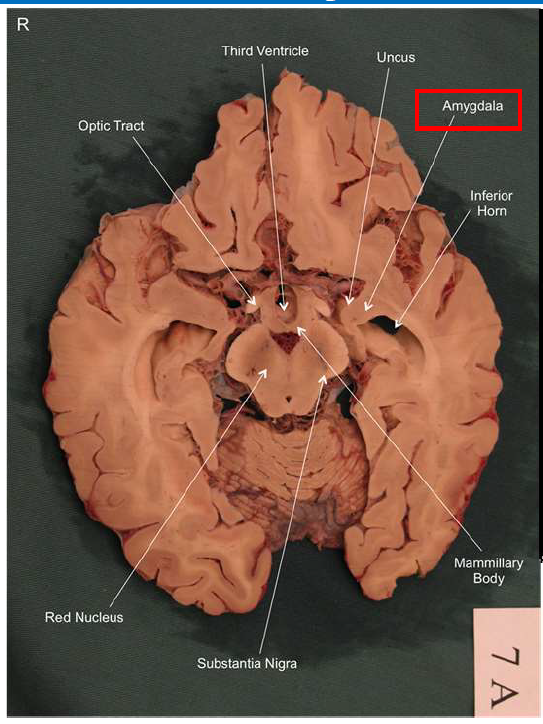

What is the fornix of the hippocampus?

Hippocampus output pathway (C-shaped)

Connects hippocampus to hypothalamus/mamillary bodies

Carries information to and from hippocampus

Important for memory consolidation and retrieval

What is this?

hippocampal fornix